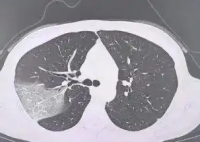

女子硬扛高烧3天变白肺 为什么这么严重?

流感不过是一场重感冒,吃点药休息休息就能好?39岁的程女士(化名)是名工作狂,在熬夜爆肝工作的同时还保持着异常纤细的身姿。感冒后,她硬